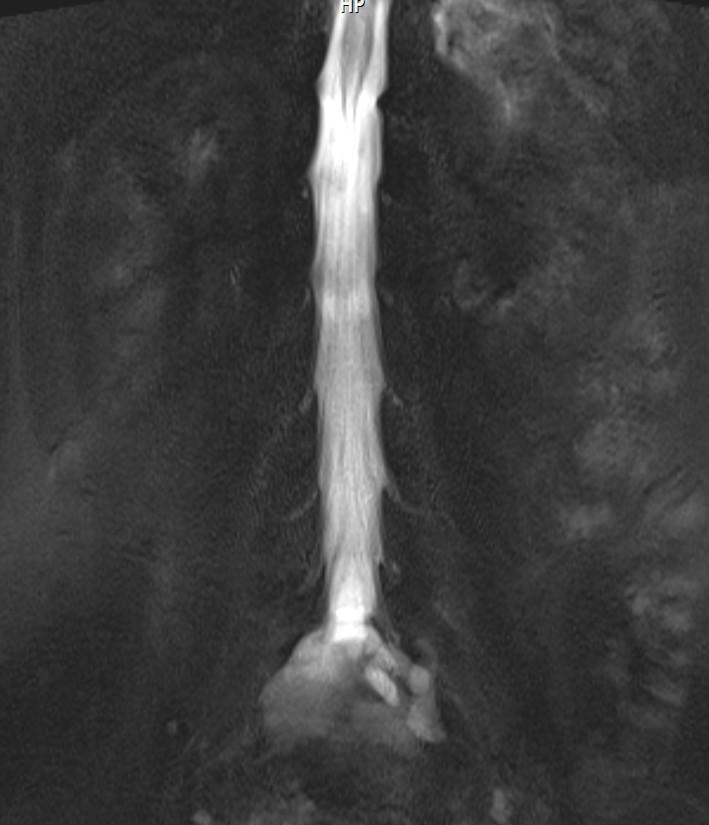

Answer: Occult intrasacralmeningocele

MR images demonstrated large cystic lesion in the sacral canal.

Occult intrasacralmeningoceletypically appear hypodenselesion (isodense to CSF) enlarging the sacral thecal sac which may displace the nerve roots.

MRI is the best modality to assess an occult intrasacralmeningocele.

• T2: hyperintense (isointense to CSF)